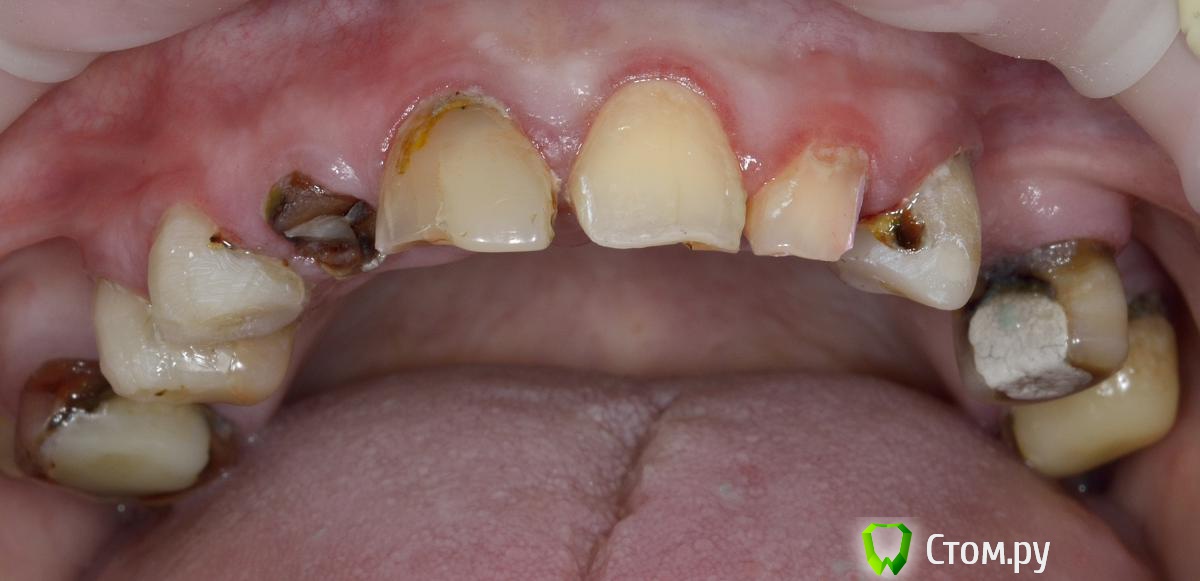

Vitremer Опубликовано 13 июля, 2014 Поделиться Опубликовано 13 июля, 2014 Здравствуйте! Пациентка 37 лет. Тотальное протезирование в/ч.Что делать:1.с уже ранее леченными и восстановлеными СВШ зубами 1.4 1.3 2.3 2.7 ? ( оставлять-менять на вкв...)2. корень 1.2 . ВКВ ? феррула почти нетПока такие вопросы. Ссылка на комментарий

Евгений Ходыкин Опубликовано 13 июля, 2014 Поделиться Опубликовано 13 июля, 2014 Имхо 1.7, 1.6, 1.2 аут, судьба остальных после рентгена... Ссылка на комментарий

Alex74 Опубликовано 13 июля, 2014 Поделиться Опубликовано 13 июля, 2014 (изменено) Давайте без сарказма. Пока она будет собирать на две челюсти-полетит все оставшееся. А импланты-совсем другой прайсНикакого сарказма. БОльшая часть зубов, судя по фото, очень сильно разрушена. Качественно их сделать будет стоить не дешевле имплантатов. Если перебирать их дорого, то тогда "более-менее" нормальные зубы - это резцы 11 21 22 и премоляр слева. Какие варианты бюджетные приходят в голову с 4 оставшимися во рту зубами? А ставить "на то что было, то и полюбила"...ну не знаю. Сколько оно простоит? Поэтому простое решение предложил - всё убрать и сделать ПСП. Изменено 13 июля, 2014 пользователем Alex74 Ссылка на комментарий